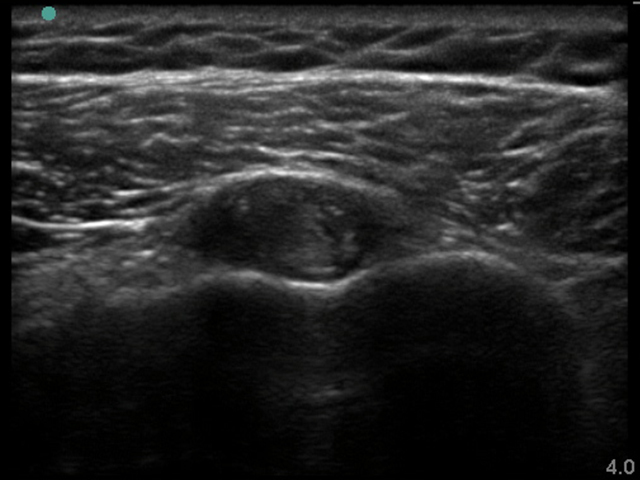

Image - Épaule : Ténosynovite du biceps